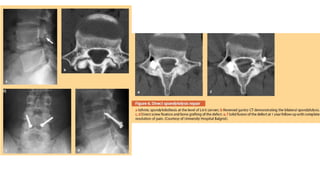

Reparacion directa dela pars -En paciente jovenes sin evidencia de degeneracion discal o de la misma listesis Key operative: -Desbridacion el tejido hipertrofia blando en la pars -Escarificacion del defecto -Adecuada compresion y estabilidad al defecto mediante osteosintesis.